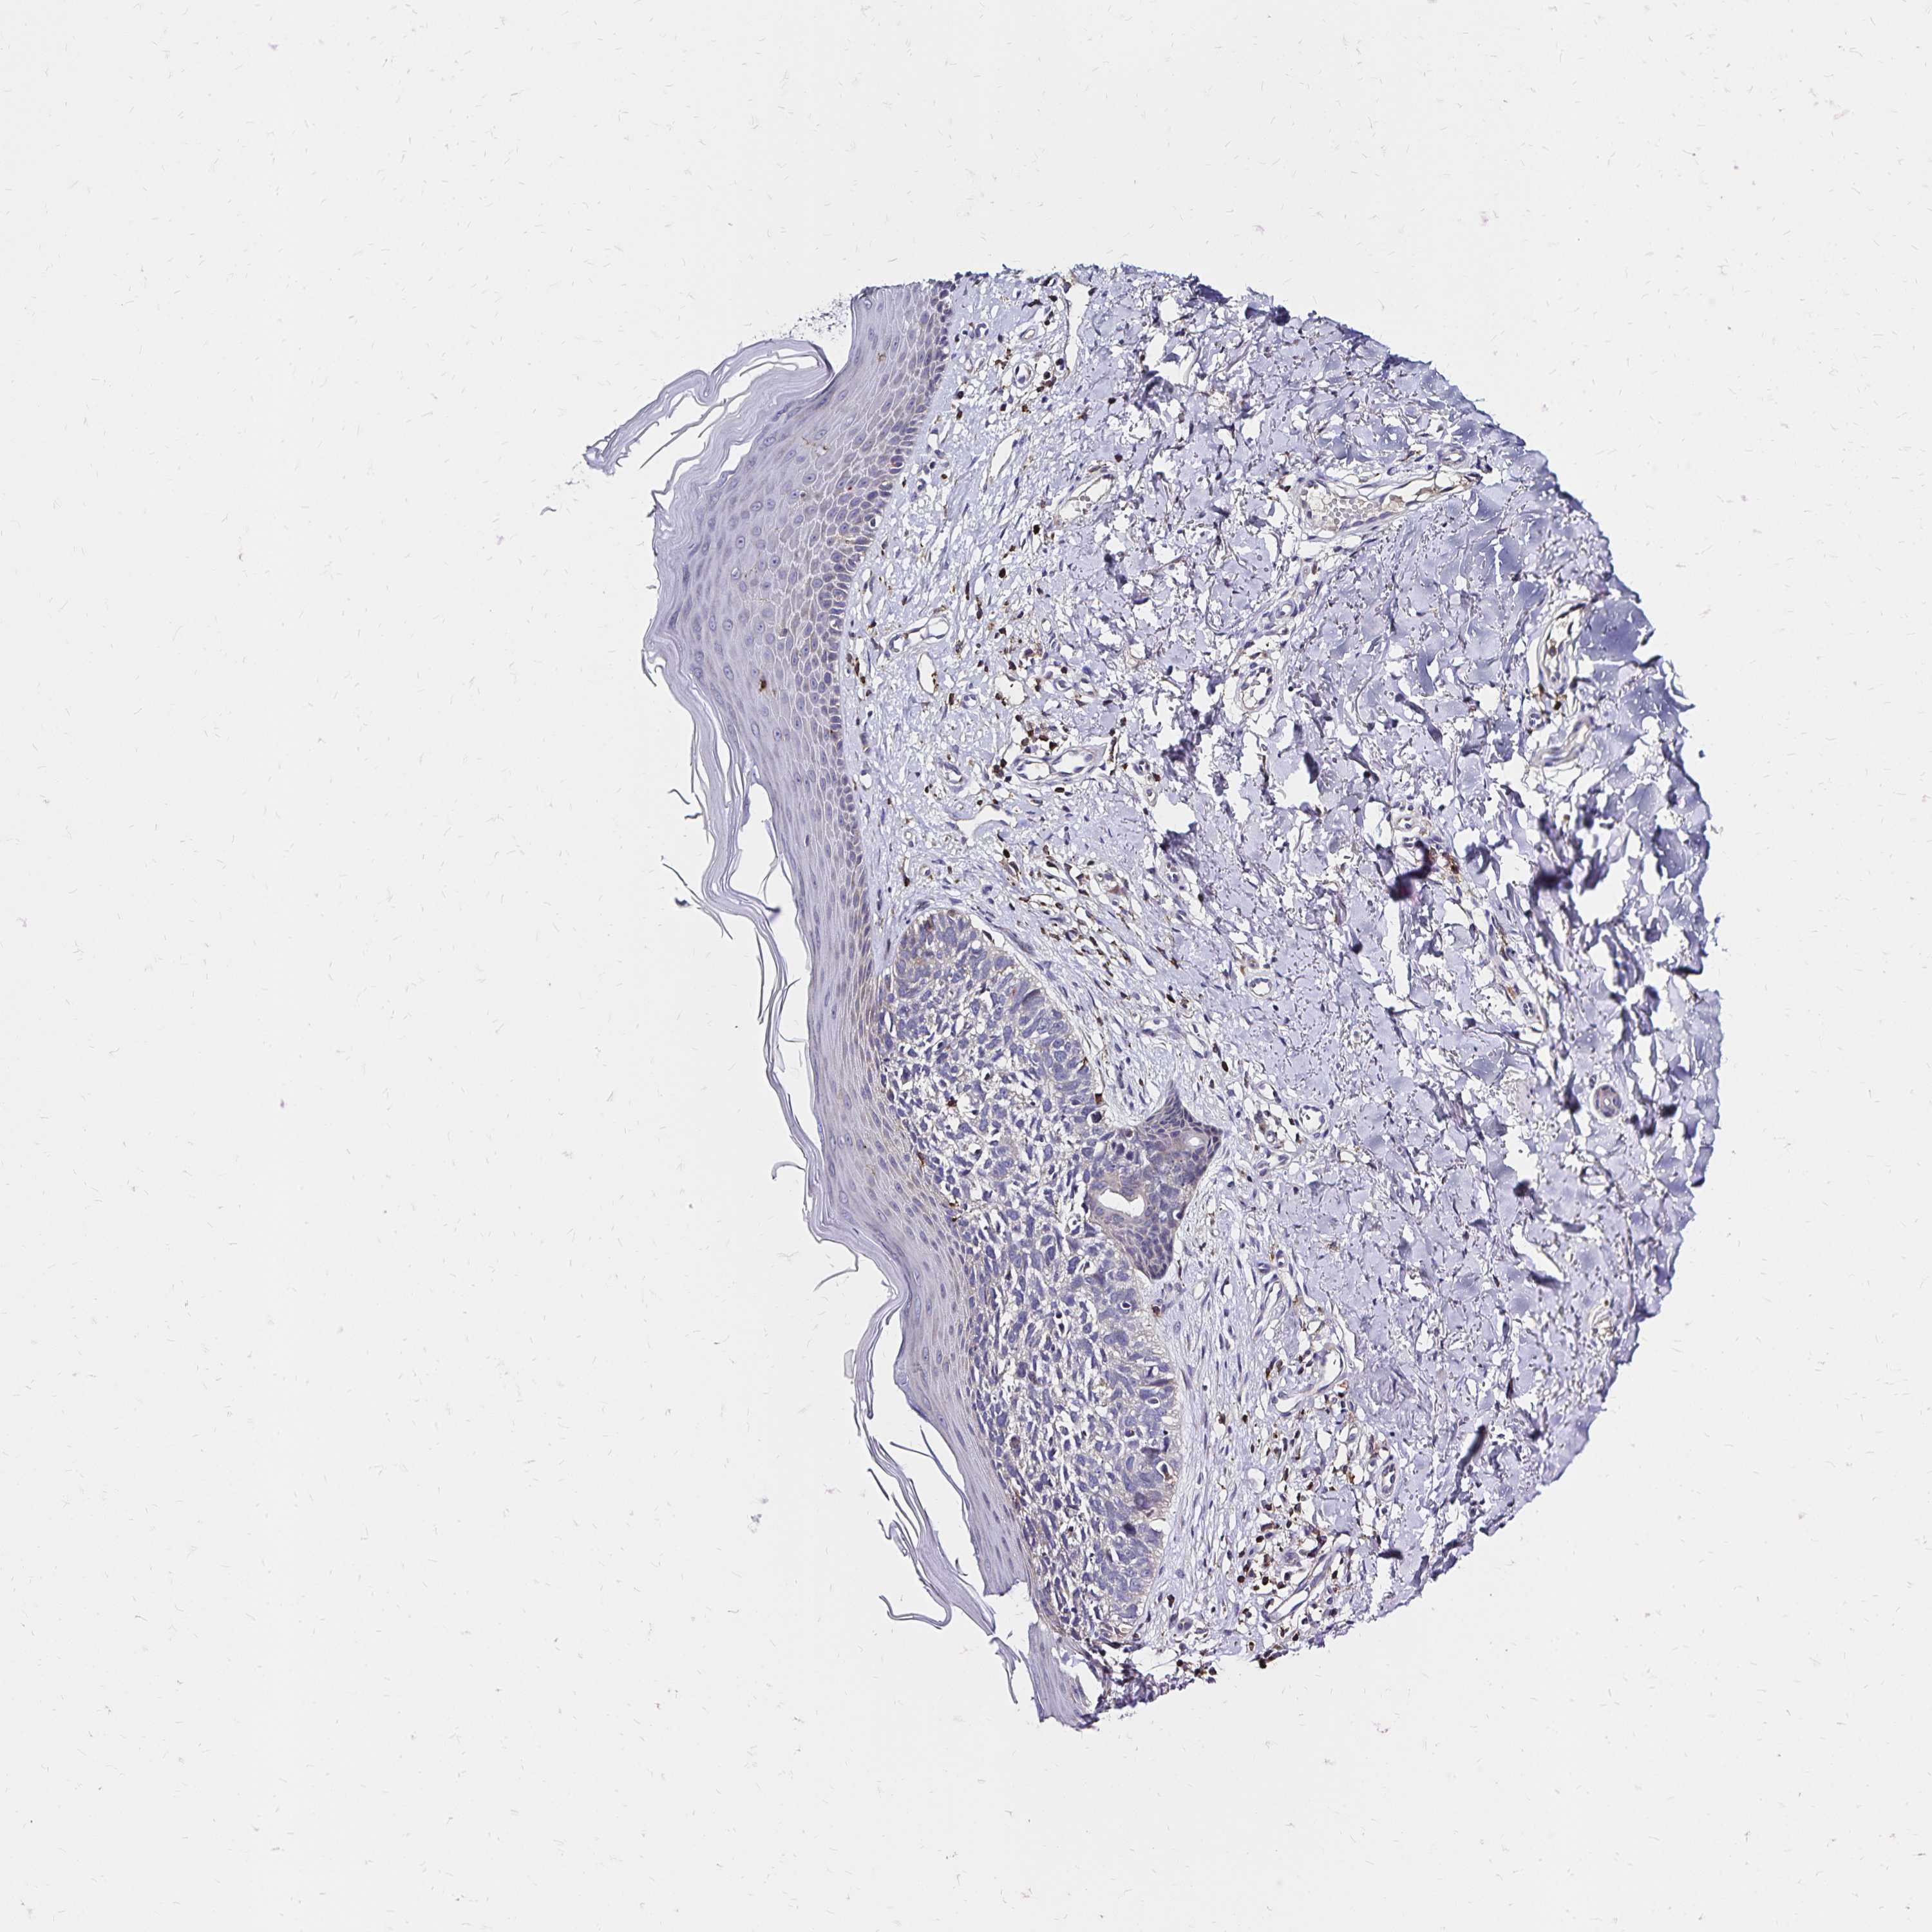

SKIN CANCER - Protein expressioni

A mouse-over function shows sample information and annotation data. Click on an image to view it in a full screen mode. Samples can be filtered based on level of antibody staining by selecting one or several of the following categories: high, medium, low and not detected. The assay and annotation is described here.

Antibody stainingi

Antibody staining in the annotated cell types in the current human tissue is reported as not detected, low, medium, or high, based on conventional immunohistochemistry profiling in selected tissues. This score is based on the combination of the staining intensity and fraction of stained cells.

Each image is clickable and will lead to virtual microscopy that enables deeper exploration of all samples and also displays staining intensity scores, fraction scores and subcellular localization as well as patient and tissue information for each sample.

Antibody HPA064055

Staining

High

Medium

Low

Not detected

Intensity

Strong

Moderate

Weak

Negative

Quantity

>75%

75%-25%

<25%

None

Location

Nuclear

Cytoplasmic/membranous

Cytoplasmic/membranous,nuclear

Basal cell carcinoma

Squamous cell carcinoma, NOS